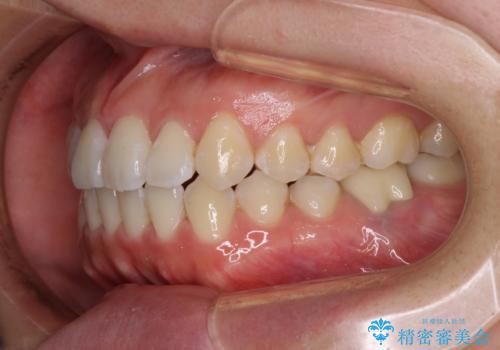

前歯のデコボコを治したい ワイヤー矯正

- 前歯のデコボコが気になるとのことで来院された患者様です。

目立たない装置と金属のワイヤーで矯正治療を行うこととしました。

1年半程度の期間を見込んでいましたが、上下の真ん中の位置をできる限り合わせるための調整に少し時間がかかってしまいました。

咬み合わせが安定し、前歯の汚れも付きにくくなりました。